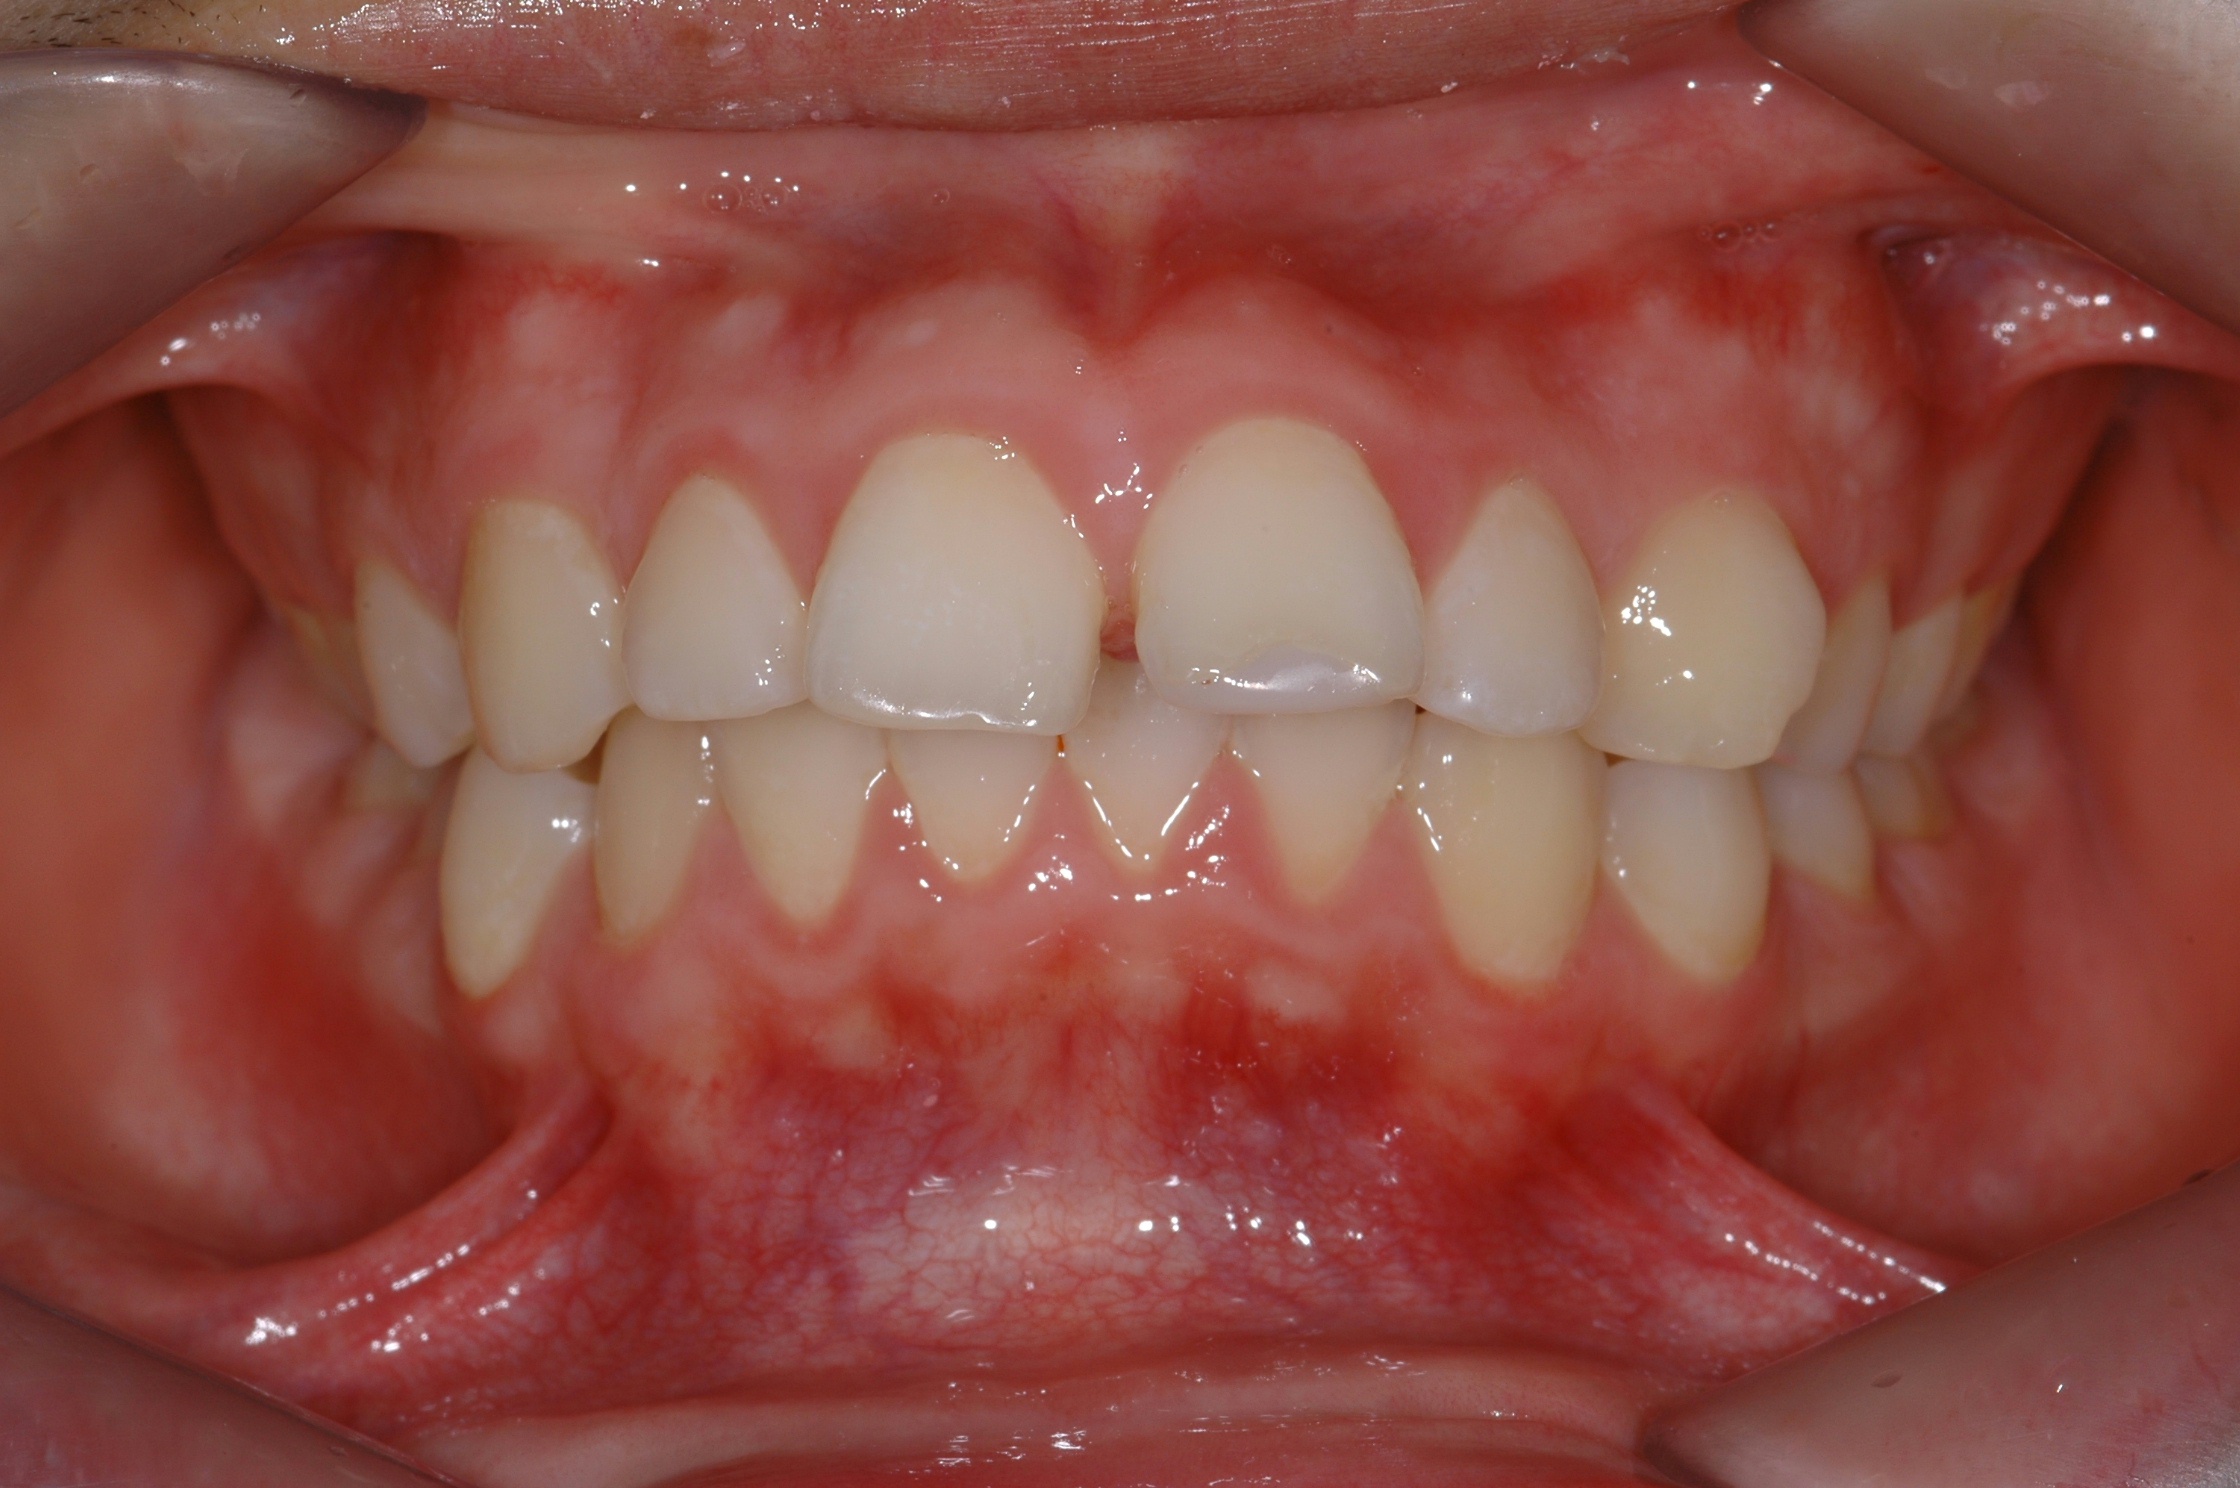

치료 전 사진입니다.